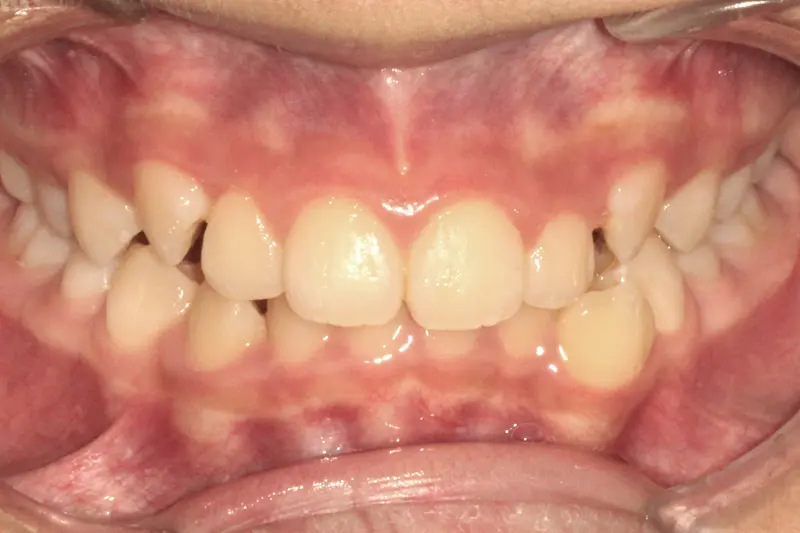

The Diagnosis

Severe crowding with blocked-out permanent teeth. The jaw size was insufficient to accommodate the erupting adult teeth, leading to significant rotation and displacement.

The Engineering

By intervening early, we utilized rapid palatal expansion to develop the arch width. This created the necessary space for the permanent teeth to erupt naturally, avoiding the need for future extractions.

Before treatment: The Expansion Phase

Before